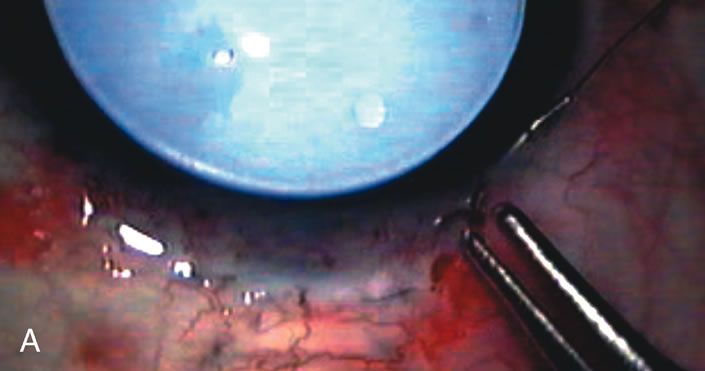

In years past, patients with both cataract and glaucoma frequently provided overwhelming surgical challenges for the ophthalmologist. The ability to carry out phacoemulsification through a 3.2-mm corneal incision along with inserting a foldable IOL is a vast improvement over 11-mm incisions that were common a decade ago (Fig. 1). The anatomical and inflammatory changes to the eye are less with small incision techniques, improving the likelihood of success with concomitant glaucoma surgery. Pharmacologic inhibition of fibrosis along with postoperative wound revision increases the long-term success rate of filtration surgery when combined with lens extraction. (Fig. 2). The learning curve may be steep at times, but the blending of cataract and glaucoma surgical skills slowly falls into place as the surgeon constantly learns and upgrades his or her technique.

Fig. 2. Wound modulation and revision. A. MMC decreases the likelihood of bleb failure in high-risk eyes undergoing combined cataract and glaucoma surgery. Overusage of this potent cytotoxic drug should be avoided owing to a myriad of problems related to the formation of an avascular bleb. B. Office-based laser revision of the operative wound allows for increased postoperative flexibility with less complications. The correct number and tension of scleral flap sutures allows the surgeon to strive for a safe immediate postoperative IOP range. When fibrosis occurs at approximately 1 week, suturelysis or release of sutures increases filtration while avoiding unwanted hypotony.